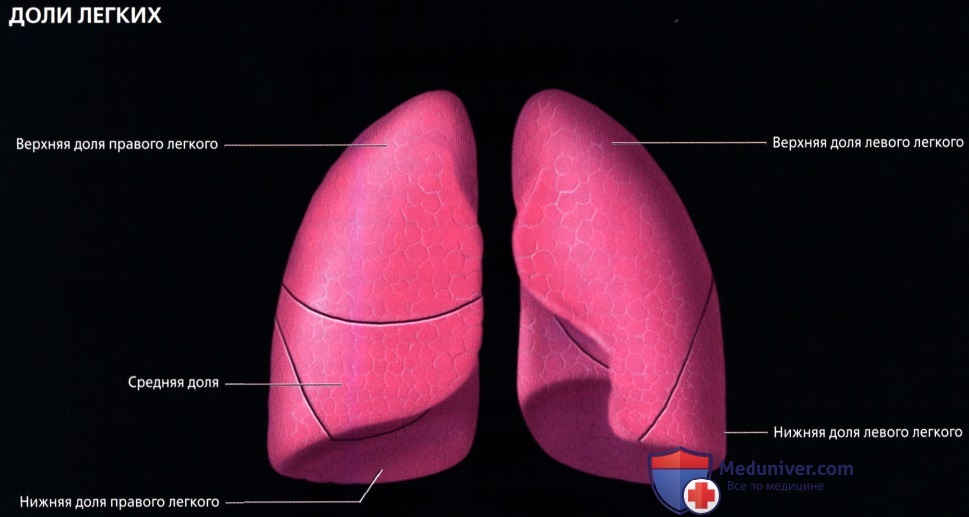

Анатомические изображения сегментов легких различных животных

Раздел: Другие животные